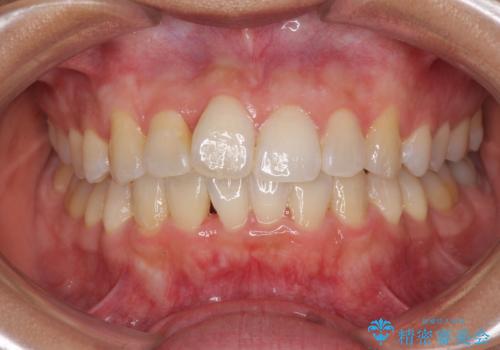

前歯のデコボコをインビザラインでスッキリと仕上げる

- 上下前歯のデコボコと奥歯の銀歯を気にして来院された患者様です。

口元をインビザラインにより歯列を整え、その後に失活している奥歯をオールセラミッククラウンにて補綴治療することとしました。

長時間のマウスピース装着に協力いただき、自然な口元に仕上げることができました。

気になっていた銀歯もオールセラミッククラウンで本物の歯のようになり、患者様には大変満足していただきました。